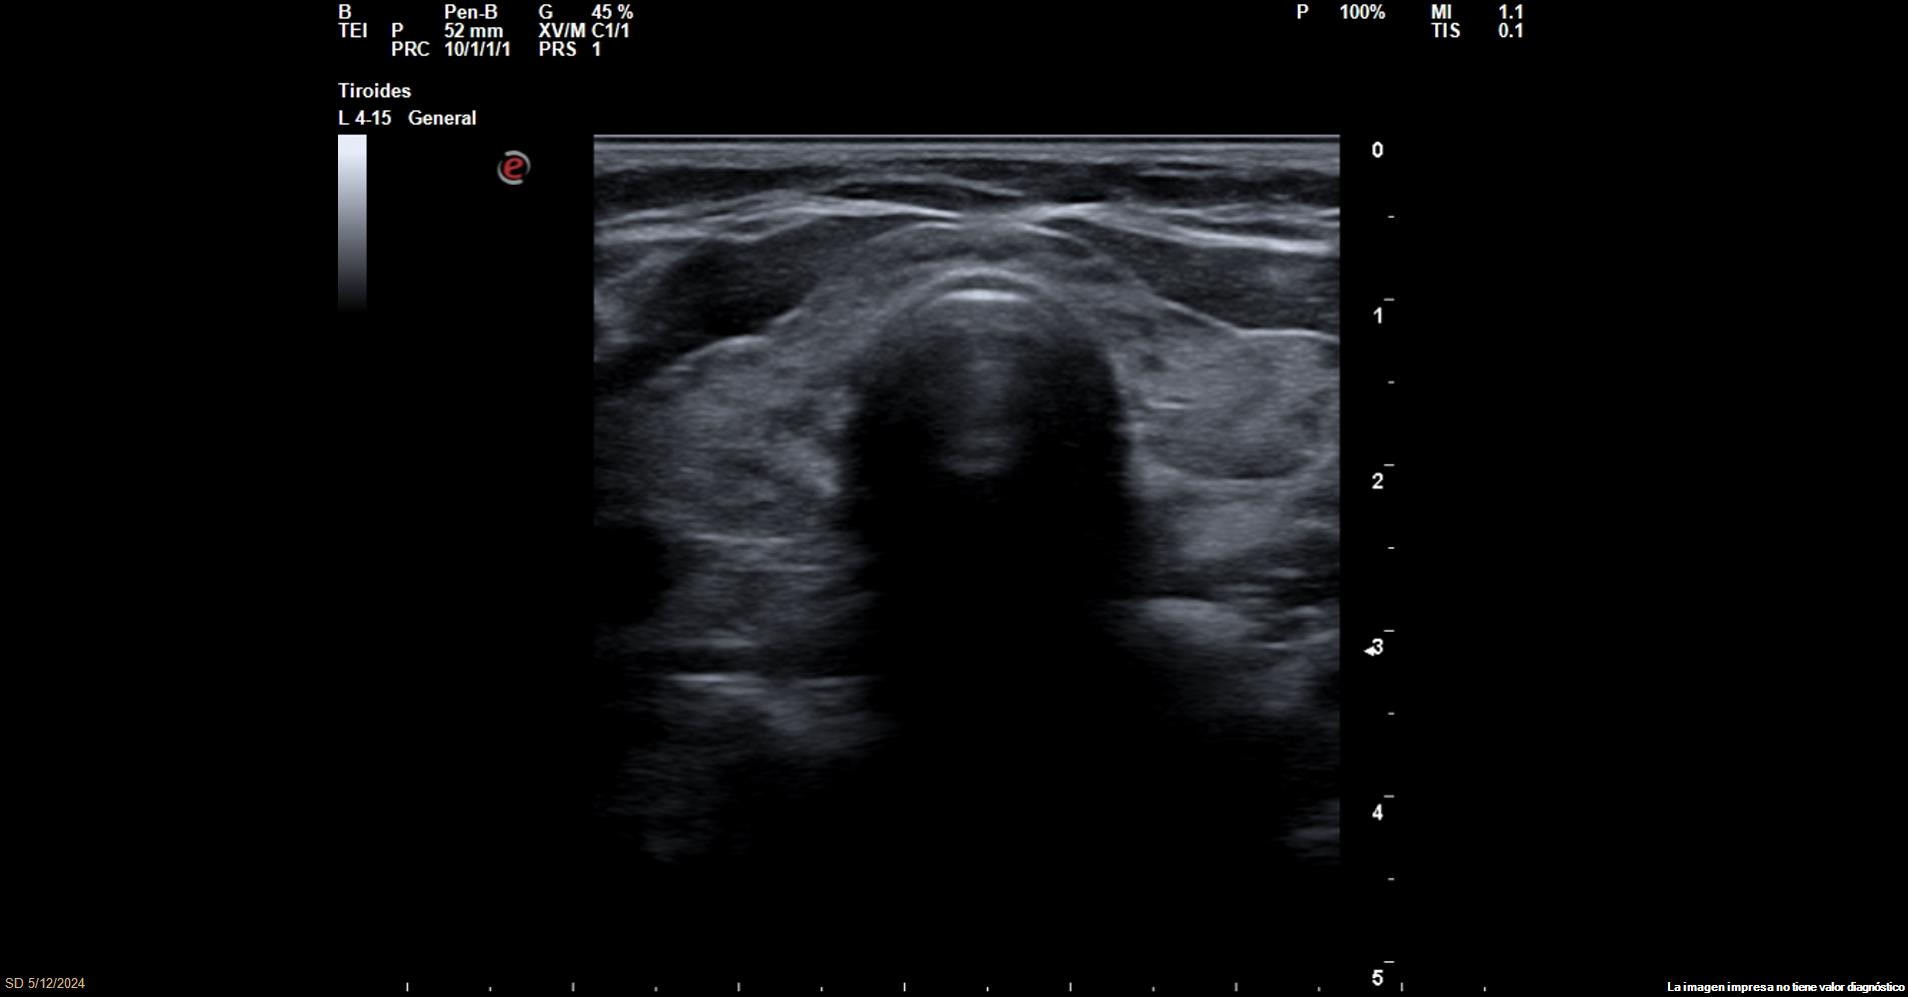

Se realiza una ecografía en el Centro de Atención Primaria donde se visualiza:

Lóbulo derecho de contorno regular, parénquima heterogéneo de aspecto atigrado. Doppler (+) con medidas de 12,5 x 34 mm (AP-L)

Lóbulo izquierdo de contorno regular, parénquima heterogéneo de aspecto atigrado. Doppler (+) con medidas de 13,9 x 32,5 mm(P-L).

Istmo ecográfico conservado 3,4 mm de ancho. No se observan actualmente adenopatías regionales.

Imagen nodular en polo inferior LTE, sugestiva de paratiroides de 4,3 mm.

Conclusión: Examen con tiroiditis/adenoma paratiroides.